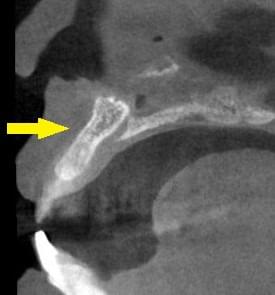

さらに、CTで、別な方向から見ると、黄色矢印のように骨が吸収されていて、緑色矢印で示される神経の通る管に迫り、インプラントが埋入できるような骨量はありませんでした。

インプラントを埋入するために、骨を増やす方法はいくつかありましたが、この場合、患者様ご自身の骨をブロック状で移植するのが最も適していると判断し、自家骨移植術を行ないました。患者様ご自身の下顎前歯の下方から骨を採取して、骨がなかった部位に移植し、スクリューで固定したCT画像です。黄色矢印部分が、2つの骨片を移植して、固定したところです。